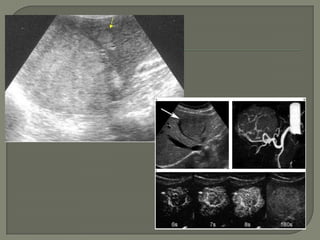

 Ojo  de toro o diana: zona hipoecoica

periférica

 Frec en carcinoma broncógeno.

 Ojo de toro o diana: zona hipoecoica periférica  Frec en carcinoma broncógeno.